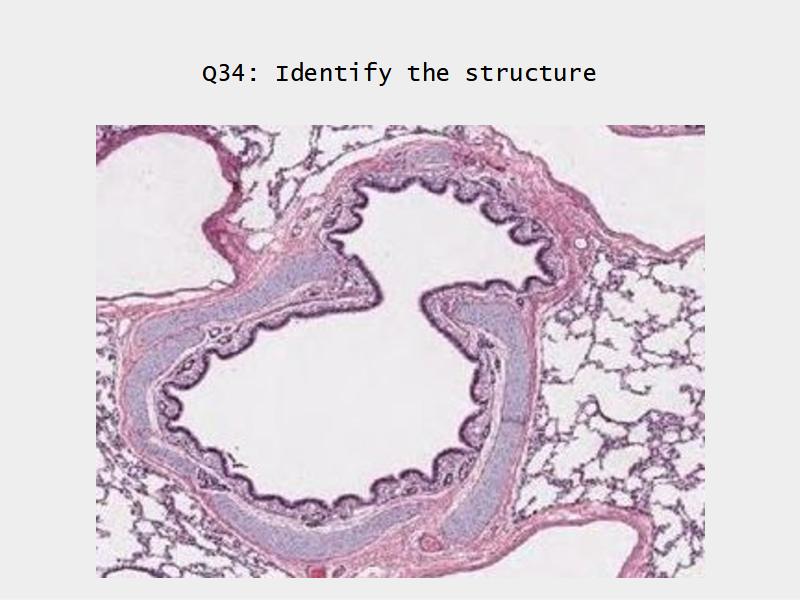

Bronchi - Transitions

- Intrapulmonary bronchi

- Irregular cartilage

- Respiratory epithelium

- Glands

- Bronchioles

- Smooth muscle REPLACE cartilage

- Ciliated columnar > Ciliated cuboidal

- NO glands - goblet cells -> secretory cells

- Terminal bronchioles

- Smooth muscle

- Ciliated cuboidal epithelium

- Secretory cells